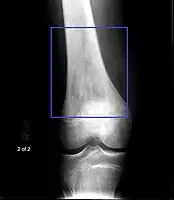

X-ray of osteosarcoma of the distal femur in a dog

Osteosarcomas tend to occur at the sites of bone growth, presumably because proliferation makes osteoblastic cells in this region prone to acquire mutations that could lead to transformation of cells (the RB gene and p53 gene are commonly involved). Due to this tendency, high incidence of osteosarcoma is seen in some large dog breeds (St. Bernards and Great Danes). The tumor may be localized at the end of the long bone (commonly in the metaphysis). Most often it affects the proximal end of tibia or humerus, or distal end of femur. Osteosarcoma tends to affect regions around the knee in 60% of cases, 15% around the hip, 10% at the shoulder, and 8% in the jaw. The tumor is solid, hard, irregular ("fir-tree," "moth-eaten", or "sun-burst" appearance on X-ray examination) due to the tumor spicules of calcified bone radiating in right angles. These right angles form what is known as a Codman triangle, which is characteristic but not diagnostic of osteosarcoma. Surrounding tissues are infiltrated.

Family physicians and orthopedists rarely see a malignant bone tumor (most bone tumors are benign). The route to osteosarcoma diagnosis usually begins with an X-ray, continues with a combination of scans (CT scan, PET scan, bone scan, MRI) and ends with a surgical biopsy. A characteristic often seen in an X-ray is Codman's triangle, which is basically a subperiosteal lesion formed when the periosteum is raised due to the tumor. Films are suggestive, but bone biopsy is the only definitive method to determine whether a tumor is malignant or benign.